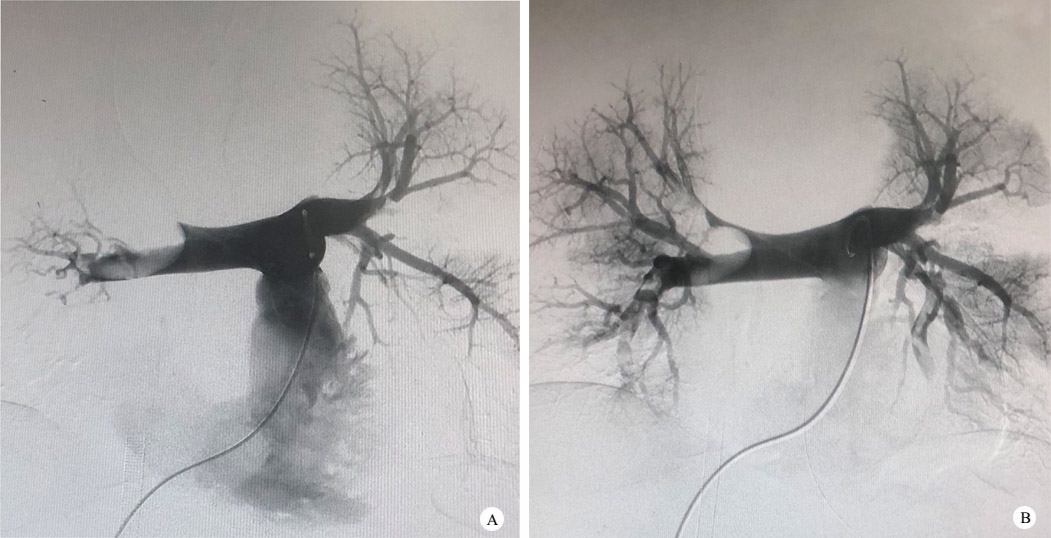

转入本院时患者体温37.5℃,呼吸15次/min(呼吸机辅助通气),心率125次/min,血压60/38 mmHg[以去加肾上腺素1.3μg/(Kg•min)维持,1 mmHg=0.133 kPa],SOFA评分18分。心超提示右室增大,“O”型心,EF 15%。入院诊断:肺栓塞、呼吸心搏骤停、复苏后综合征。经家属充分知情同意后,纳入“评价心肺转流系统用离心泵(体外膜肺氧和设备)的有效性及安全性:一项前瞻性、多中心、单臂临床试验(版本号:V3.0/20221021)”,项目所用离心泵为湖州露湖鄱生物科技公司研发,主机规格RP-2,体外循环套包泵头BE-PLS 2050(MAQUET,国械注进20163104678)。右侧股静脉置入22F导管,左侧股动脉置入16F导管。置管成功后连接预冲管路,采V-A模式,转速4 000 rpm维持,流量3.3 L/min(见附图 1)。ECMO支持下予“肺动脉造影术+双侧肺动脉血栓吸除术”,术中见右肺动脉主干闭塞,右肺动脉分支未见显影,左侧肺动脉分支可见多发充盈缺损(图 2A),证实右肺动脉主干栓塞+左肺动脉分支栓塞。经Angiojet吸栓导管测右肺动脉压力45 mmHg。左肺动脉分支、右肺动脉主干及三分支吸栓,Angiojet导管吸栓后见两侧肺动脉主干及右肺动脉三分支显影明显(图 2B),测右肺动脉压力17 mmHg。入院后即行取栓术(见附图 2),术中患者再发心搏骤停2次,每次持续约1 min。VA-ECMO运行顺利,无不良情况发生。取栓完成后患者肺动脉压力明显减轻,血流动力学改善明显,患者收住本院急诊监护室严密监护。

| A: 肺动脉造影显示右肺动脉主干栓塞; B: 取栓术后肺动脉造影显示右肺动脉再通 图 2 取栓术前术后肺动脉造影 |